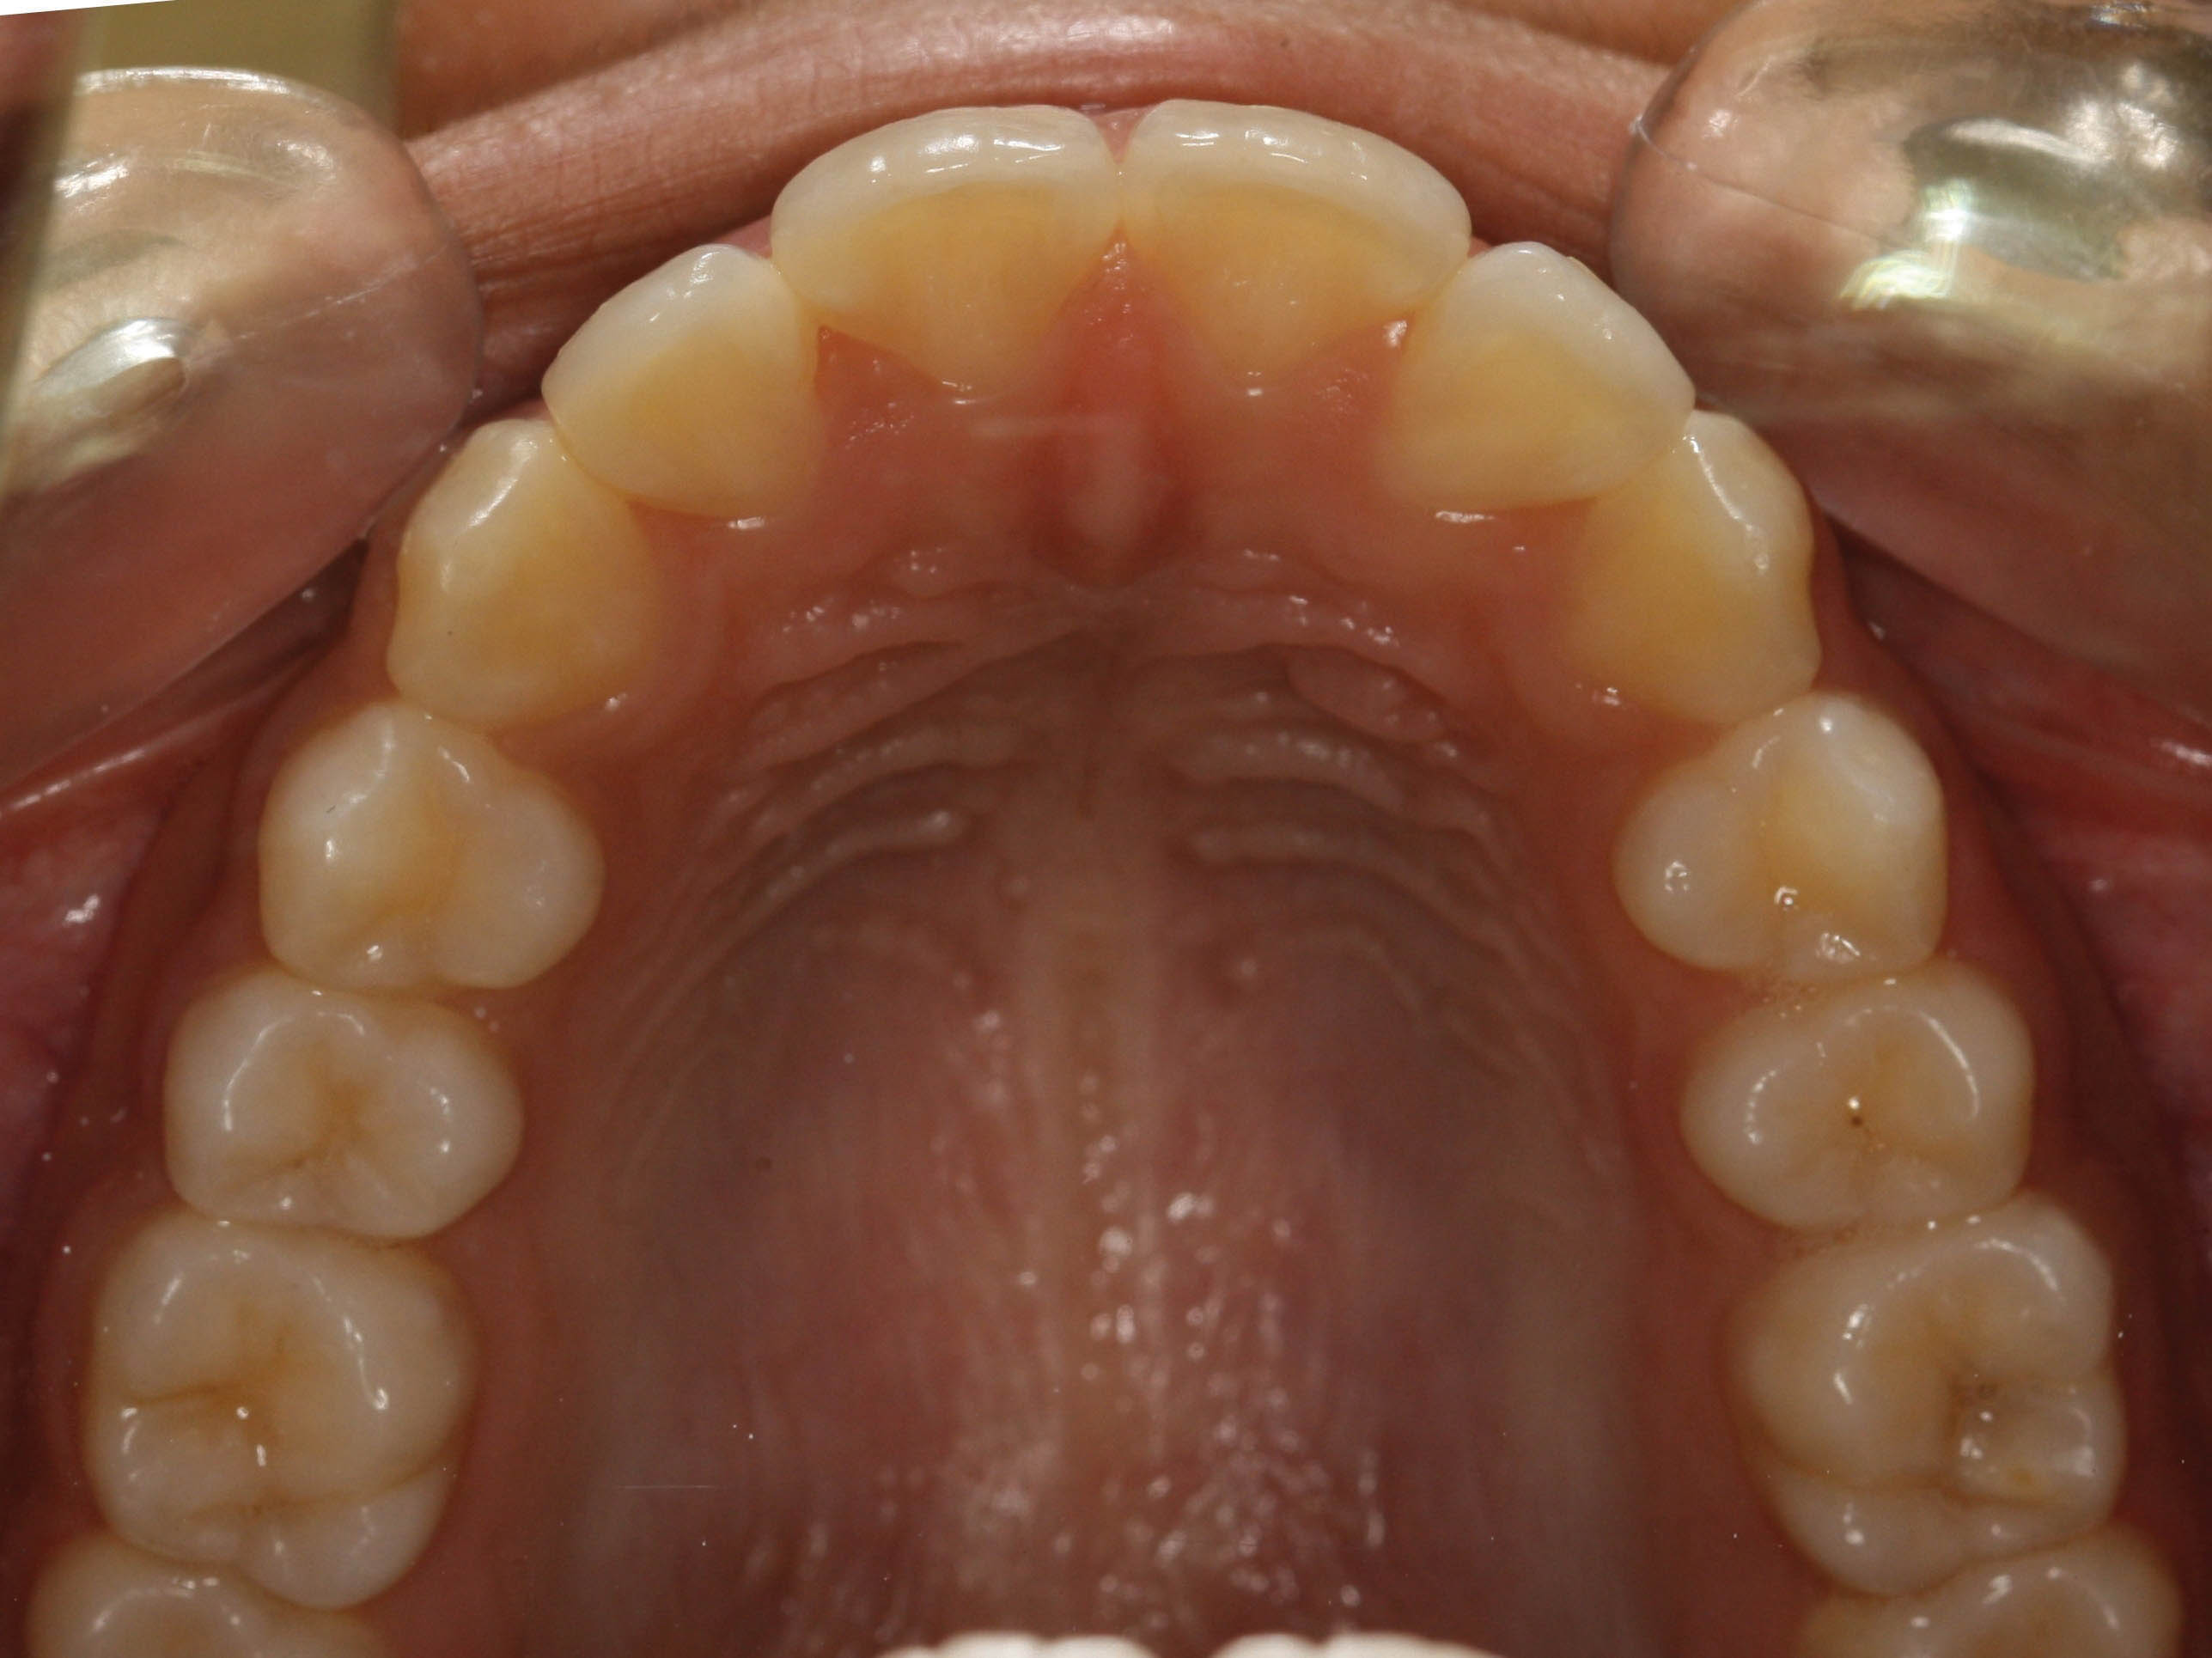

بعد از درمان